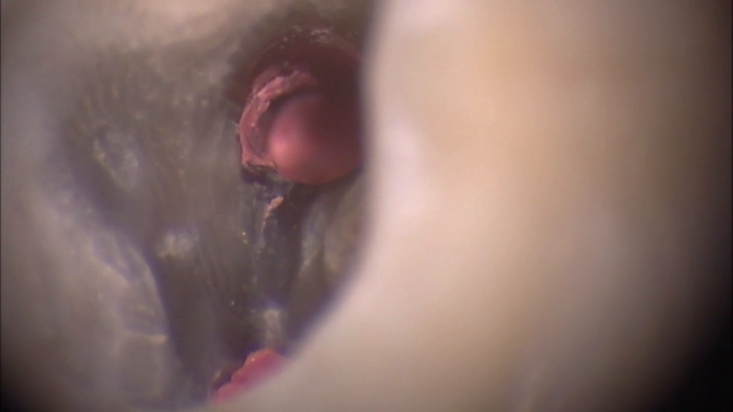

Сл. 38.14

Сл. 38.14 а) Предоперативна радиографија на долен лев втор молар. Она што се чини дека е латерален канал на коронарната третина од мезијалниот канал, всушност е некој оптурациски материјал што влегува во пропуштениот мезиолингвален канал: Латералните канали на коронарната третина обично потекнуваат со агол од 90°, додека остриот агол е типичен за апикалниот дел од коренскиот канал. б) Пристапен кавитет: Мезиолингвалниот дентин го крие отворот на мезиолингвалниот канал. в) Дел од дентинот е отстранет со помош на ултразвучен врв под оперативен микроскоп. Гутаперката во каналниот отвор на пропуштениот канал е очигледна. г) „Тестот за шампањ“ со натриум хипохлорит ја покажува реакцијата на растворот за иригација со резидуалното ткиво во пропуштениот канал. д) Нагодување на пропуштениот канал. ѓ) Сместен конус. е) Постоперативна радиографија. Пропуштениот канал имаше независен отвор, одговорен за симптомите на пациентот.